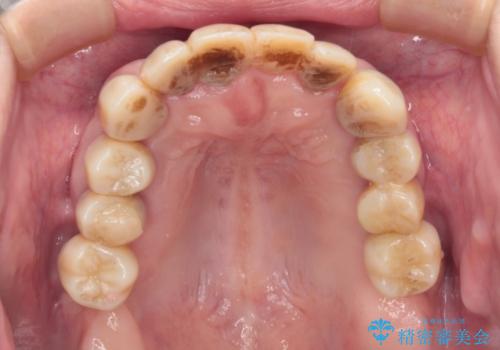

歯周病でグラグラの歯 矯正治療と歯周外科を併用した総合歯科治療

診察を行ったところ、重度歯周病の状態の上に上下の歯列が著しい叢生という状態でした。

歯周初期治療として抜歯や歯槽骨再生治療を行い、さらに歯周ポケット除去を行った後に矯正治療で歯列を整えて行くこととしました。

2~3年は早く終了する予定でしたが、途中で体調を崩されて来院されない時期が続いたため、非常に長期間の治療となりました。

上顎口蓋からの堅い歯肉を移植する角化歯肉移植術を行いたかったのですが、体調不良から実施しなかったため、最終補綴物であるオールセラミッククラウンを装着した後に、知覚過敏や境目が見てしまうといった問題が一部で発生いたしました。